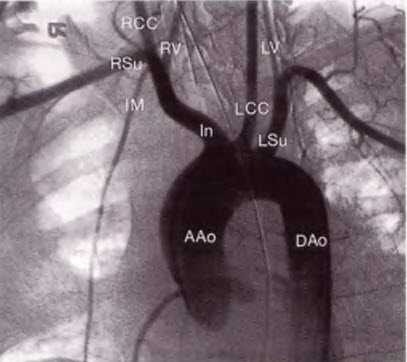

![Рис. 14.2. Дуга аорты соединяет восходящий (ААо) и нисходящий отделы аорты (DАо)]()

Рис. 14.2. Дуга аорты соединяет восходящий (ААо) и нисходящий отделы аорты (DАо). От дуги аорты отходят три крупных артериальных ствола: справа - брахиоцефальный ствол (In), левее - левая общая сонная артерия (LCC) и затем - левая подключичная артерия (LSu). Брахиоцефальный ствол делится на правую общую сонную артерию (ВСС) и правую подключичную артерию (RSu). Правая и левая позвоночные артерии (RV, LV) отходят от подключичной артерии, хотя на данной ангиограмме это не совсем четко видно. Внутренняя грудная артерия также отходит от подключичной артерии.